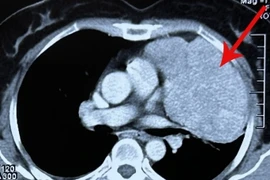

Bệnh nhân hoàn toàn khỏe mạnh, đi mổ ruột thừa phát hiện khối u trung thất lớn, phẫu thuật rất khó khăn. Đây là loại u tuyến ức không có biểu hiện ở giai đoạn sớm nên người dân cần chú ý.